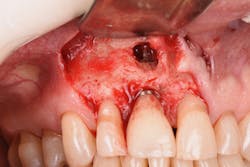

Figure 20: An osteotomy was done to access apical area of implant No. 8 utilizing the Er:YAG laser at 20 pps/70 mJ. The then-exposed area was irradiated using a combination of detoxification and biostimulation of the bone and implant to prepare the area to receive a bone graft.

Figure 21: After mechanical debridement and surface detoxification